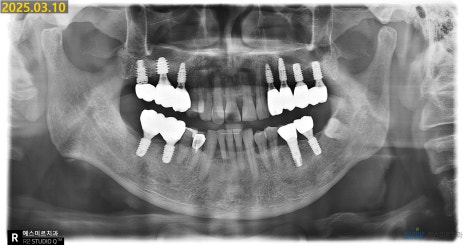

환자분은 수년 전 다른 병원에서 임플란트 치료를 받으셨는데,

최근 들어 임플란트 주변 잇몸이 자주 붓고 흔들리다가 통증이 반복돼 내원하셨습니다.

정밀 촬영과 검진 결과,

기존 임플란트 픽스처(뿌리)에 염증이 함께 발생한 상태였고

주변 골 손실도 상당해 제거 및 재수술이 필요한 상황이었습니다.